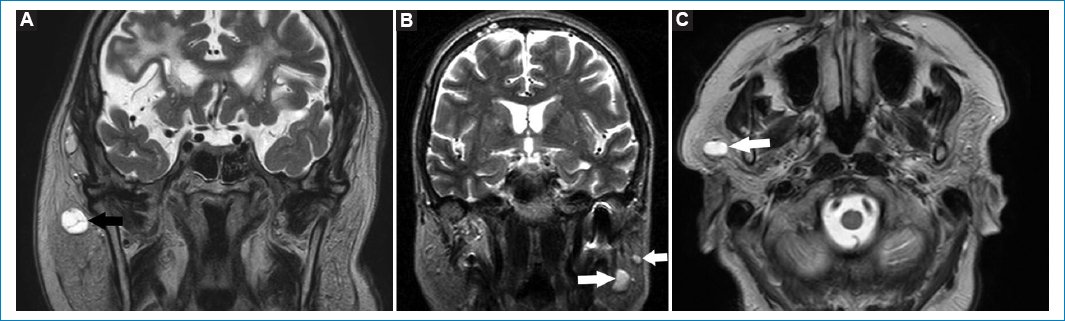

Se observan como elevaciones convexas hacia la luz de un seno paranasal, hipointensos en T1 e hiperintensos en T2 (Fig. 1)10.

Figura 1. Quiste de retención. Secuencias potenciadas en T2, cortes axiales (A-C) y coronal (D). Las flechas rellenas señalan a los QR, caracterizados como imágenes ovoideas de bordes bien delimitados, hiperintensas en T2, por su contenido líquido.